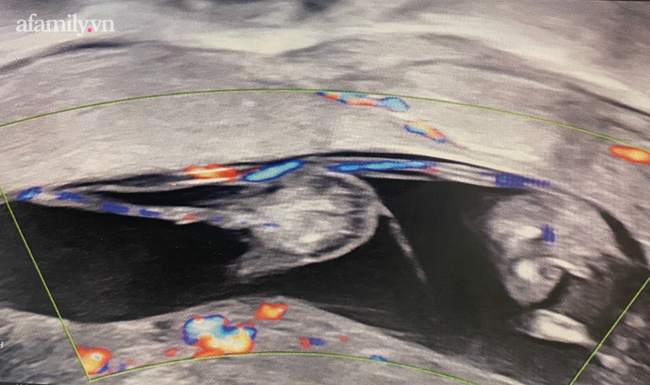

Tiến hành siêu âm, các bác sĩ thấy có dòng máu chảy từ động mạch rốn thai bình thường đi dọc mép bánh rau sang thai bất thường.

"TRAP được chẩn đoán trước sinh bằng cách siêu âm Doppler màu cho thấy lưu lượng máu đảo ngược trong động mạch rốn. Thai không tim thường có dây rốn 2 mạch máu, xuất phát từ dây rốn của thai bơm qua màng bánh rau vào thai không tim" - các bác sĩ phân tích.